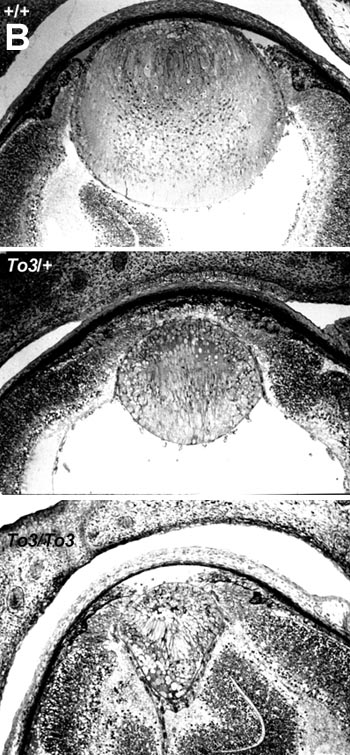

Figure 8. Histological analysis of transgenic mouse eyes

Panel A shows representative E15 eye sections. Sections of eyes from wild type (+/+), hemizygous transgenic (To3/+), and homozygous transgenic (To3/To3) siblings. Panel B shows representative E19 eye sections. Sections of eyes from wild type (+/+), hemizygous transgenic (To3/+), and homozygous transgenic (To3/To3) siblings. Panel C shows representative P18 eye sections. Sections of eyes are from hemizygous transgenic (To3/+), and homozygous transgenic (To3/To3) siblings.